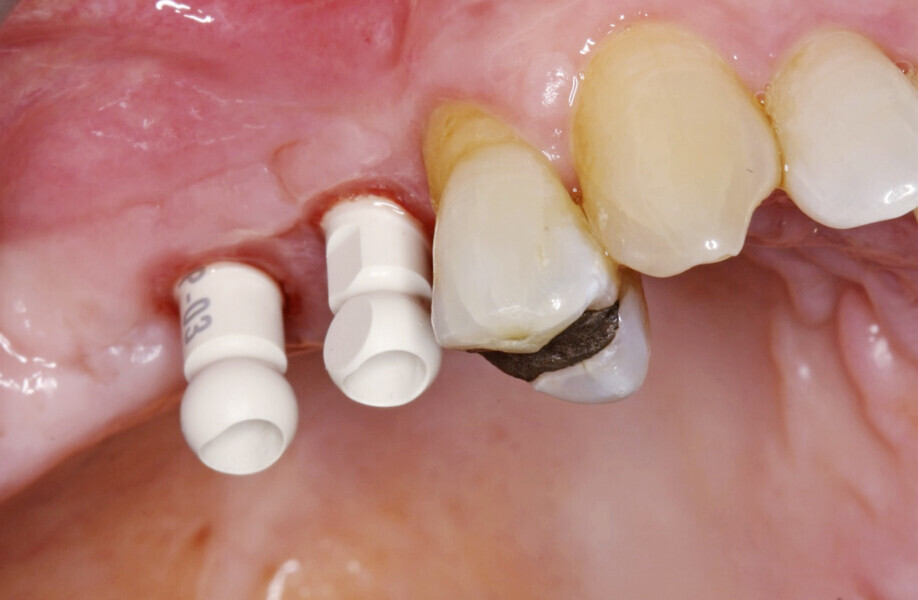

A full-thickness envelope flap was raised with relieving incisions, and the initial small round guide drill was used to mark the implant position. The site was enlarged with OmniTaper drills of different diameters, following the recommended drilling protocol. The initial osteotomy preparation was performed with a 2mm diameter OmniTaper drill at no more than 1,500 rpm and with copious external irrigation with saline according to the surgical protocol (Fig. 3). An OmniTaper EV 3.8 × 11.0 mm implant was placed in position #15 using the TempBase driver (Fig. 4). Both OmniTaper EV implants placed with the help of the preassembled TempBase abutments nicely aligned in positions #15 and 16 (Fig. 5).

Next, the large quantity of autogenous bone collected with the disposable BoneTrap (Dentsply Sirona) during surgery was used to augment the small bone fenestration (Figs. 6 & 7), and Symbios Xenograft Granules were layered over the autogenous bone (Fig. 8). Finally, Symbios Collagen Membrane SR (15 × 20 mm) was trimmed to shape to complete the guided bone regeneration procedure (Fig. 9). The wound was closed with PGA sutures (Fig. 10), and radiographic evaluation was performed to verify the implants postoperatively (Fig. 11). Three months later, medium Healing Abutments EV were placed (Fig. 12).

Fig. 5: Both OmniTaper EV implants placed with the help of the preassembled TempBase abutments nicely aligned in positions #15 and 16. Implant–abutment connection size of medium indicated in yellow.

Fig. 12: Healing Abutments EV placed at three months after initial surgery.